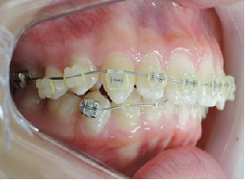

治療は上顎から矯正装置を装着していきます。

その後下顎の矯正装置を装着します。

この過程で歯並びが整いMEAW(マルチループ)を装着しやすくなります。

MEAW(マルチループ)を使用する事で上顎前突(出っ歯)や咬合高径(咬み合わせの高さ)の改善をしています。

☆治療途中